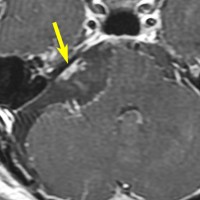

また,この患者さんは急に容態が悪くなって意識障害となりました。何故なら腫瘍の内部で出血したからです(黄色の矢印の部分)。第4脳室が詰まって閉塞性水頭症になって側脳室が拡大しています(右の画像)。

大きなのう胞性聴神経腫瘍です。いくつかの袋が重なって腫瘍を形成しています。橋や延髄(脳幹部)が変形して,第4脳室がつぶれて閉塞しています。袋の周りが白く線状に造影されているのですが,この袋の壁だけに腫瘍細胞がありますから,これを剥がすように摘出します。顔面神経が薄くなって袋の壁にくっついているのですが,袋を破ってくしゃくしゃにすると顔面神経の位置が変わってしまって,顔面神経を損傷することがあるので要注意です。のう胞性聴神経腫瘍の方が顔面神経麻痺の後遺症の頻度が高いという報告もあるくらいです。この患者さんは迷走神経と舌咽神経の圧迫も強くて,ご飯を飲み込むことが難しくなっていました(嚥下障害)。